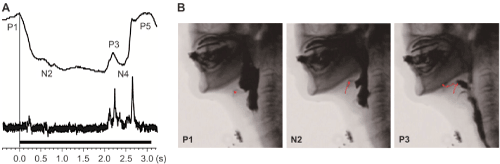

| Figure 4: Interruption of swallowing in a 72-year-old woman with Parkinson’s disease. (A) The swallowing waveform shown by the magnetic swallowing monitoring device. After the start of swallowing, the interval between P1 and P3 was approximately 2.2 s. The sound waveform nearly agreed with P3. The upper waveform represents the distance waveform, and the lower waveform represents the sound waveform. (B) On videofluorography, after the swallowing reflex had started (P1), the movement of the hyoid bone (red line) stopped with the larynx still elevated (N2). The hyoid bone then moved anteriorly, and the cricopharyngeal muscle opened. The liquid passed through the pharynx (P3). |